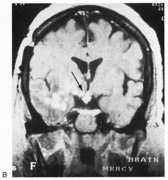

On the Boston Naming Test a subject is asked to name line drawings of objects (Fig. 22). The Visual Naming subtest of Multilingual Aphasia Exam requires the naming of photographs of objects. The Facial Recognition Test311 asks patients to select which of several pictures of faces, photographed at different angles and in different lighting conditions, match a target face (Fig. 23). Because these faces are unfamiliar, this tests face perception rather than face recognition. Face recognition can be tested by presenting pictures of presidents, movie stars, and famous athletes.